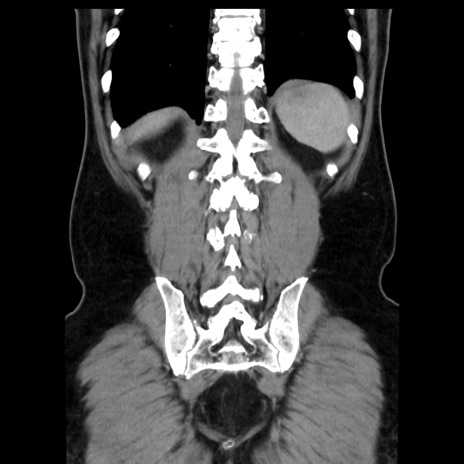

症例16(冠状断像)

【症例】 70歳代男性

【主訴】 腹痛、嘔吐

【現病歴】 約1ヶ月前より間欠的に腹痛と嘔吐あり、当院消化器内科を受診したところCTで多発する肝臓のLDAを指摘され、精査中であった。以降は消化器症状は安定していたが、2日前より嘔気と腹痛があり、同日より排便・排ガスが消失した。改善認めず、 本日、救急外来を受診した。